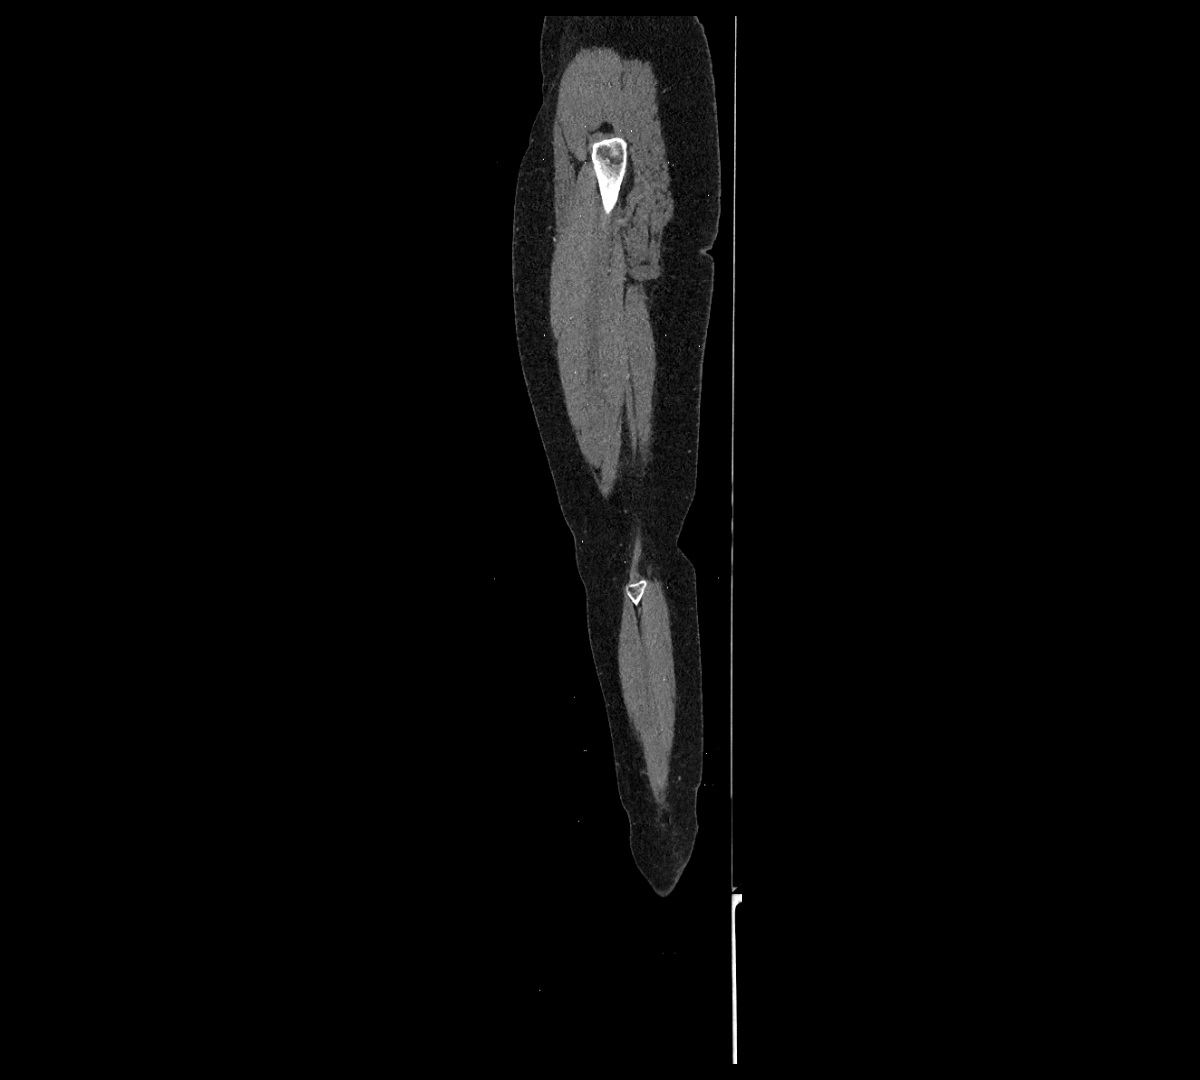

CT images

image

CT Appearance

Non-contrast CT:

• Appears as a tubular soft tissue structure anterior to vertebral bodies

• Calcified atherosclerotic plaques appear as hyperdense foci along the wall

• Useful for screening abdominal aortic aneurysm (AAA) size and mural calcification

Contrast-enhanced CT (CTA):

• Gold standard for abdominal aortic imaging

• Provides excellent detail of lumen, wall, aneurysm, thrombus, and branch vessels

• Multiplanar and 3D reconstructions help in aneurysm measurement, stent graft planning, and dissection evaluation

• Detects acute rupture, traumatic injury, or occlusion with high sensitivity